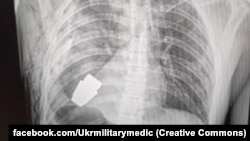

Лікарі змогли видалити гранату, яка не розірвалася, з тіла пораненого військового – про це заявило командування Медичних сил Збройних сил України 9 січня.

«Наші військові лікарі провели операцію з видалення гранати ВОГ, яка не розірвалася, з тіла військовослужбовця! Її було видалено у присутності двох саперів, які страхували безпеку медичного персоналу», – йдеться в повідомленні.

За повідомленням, операцію провів генерал-майор Андрій Верба. Вона проходила без електрокоагуляції через ризик вибуху боєприпасу.

Операція пройшла успішно, пораненого відправили на подальшу реабілітацію.